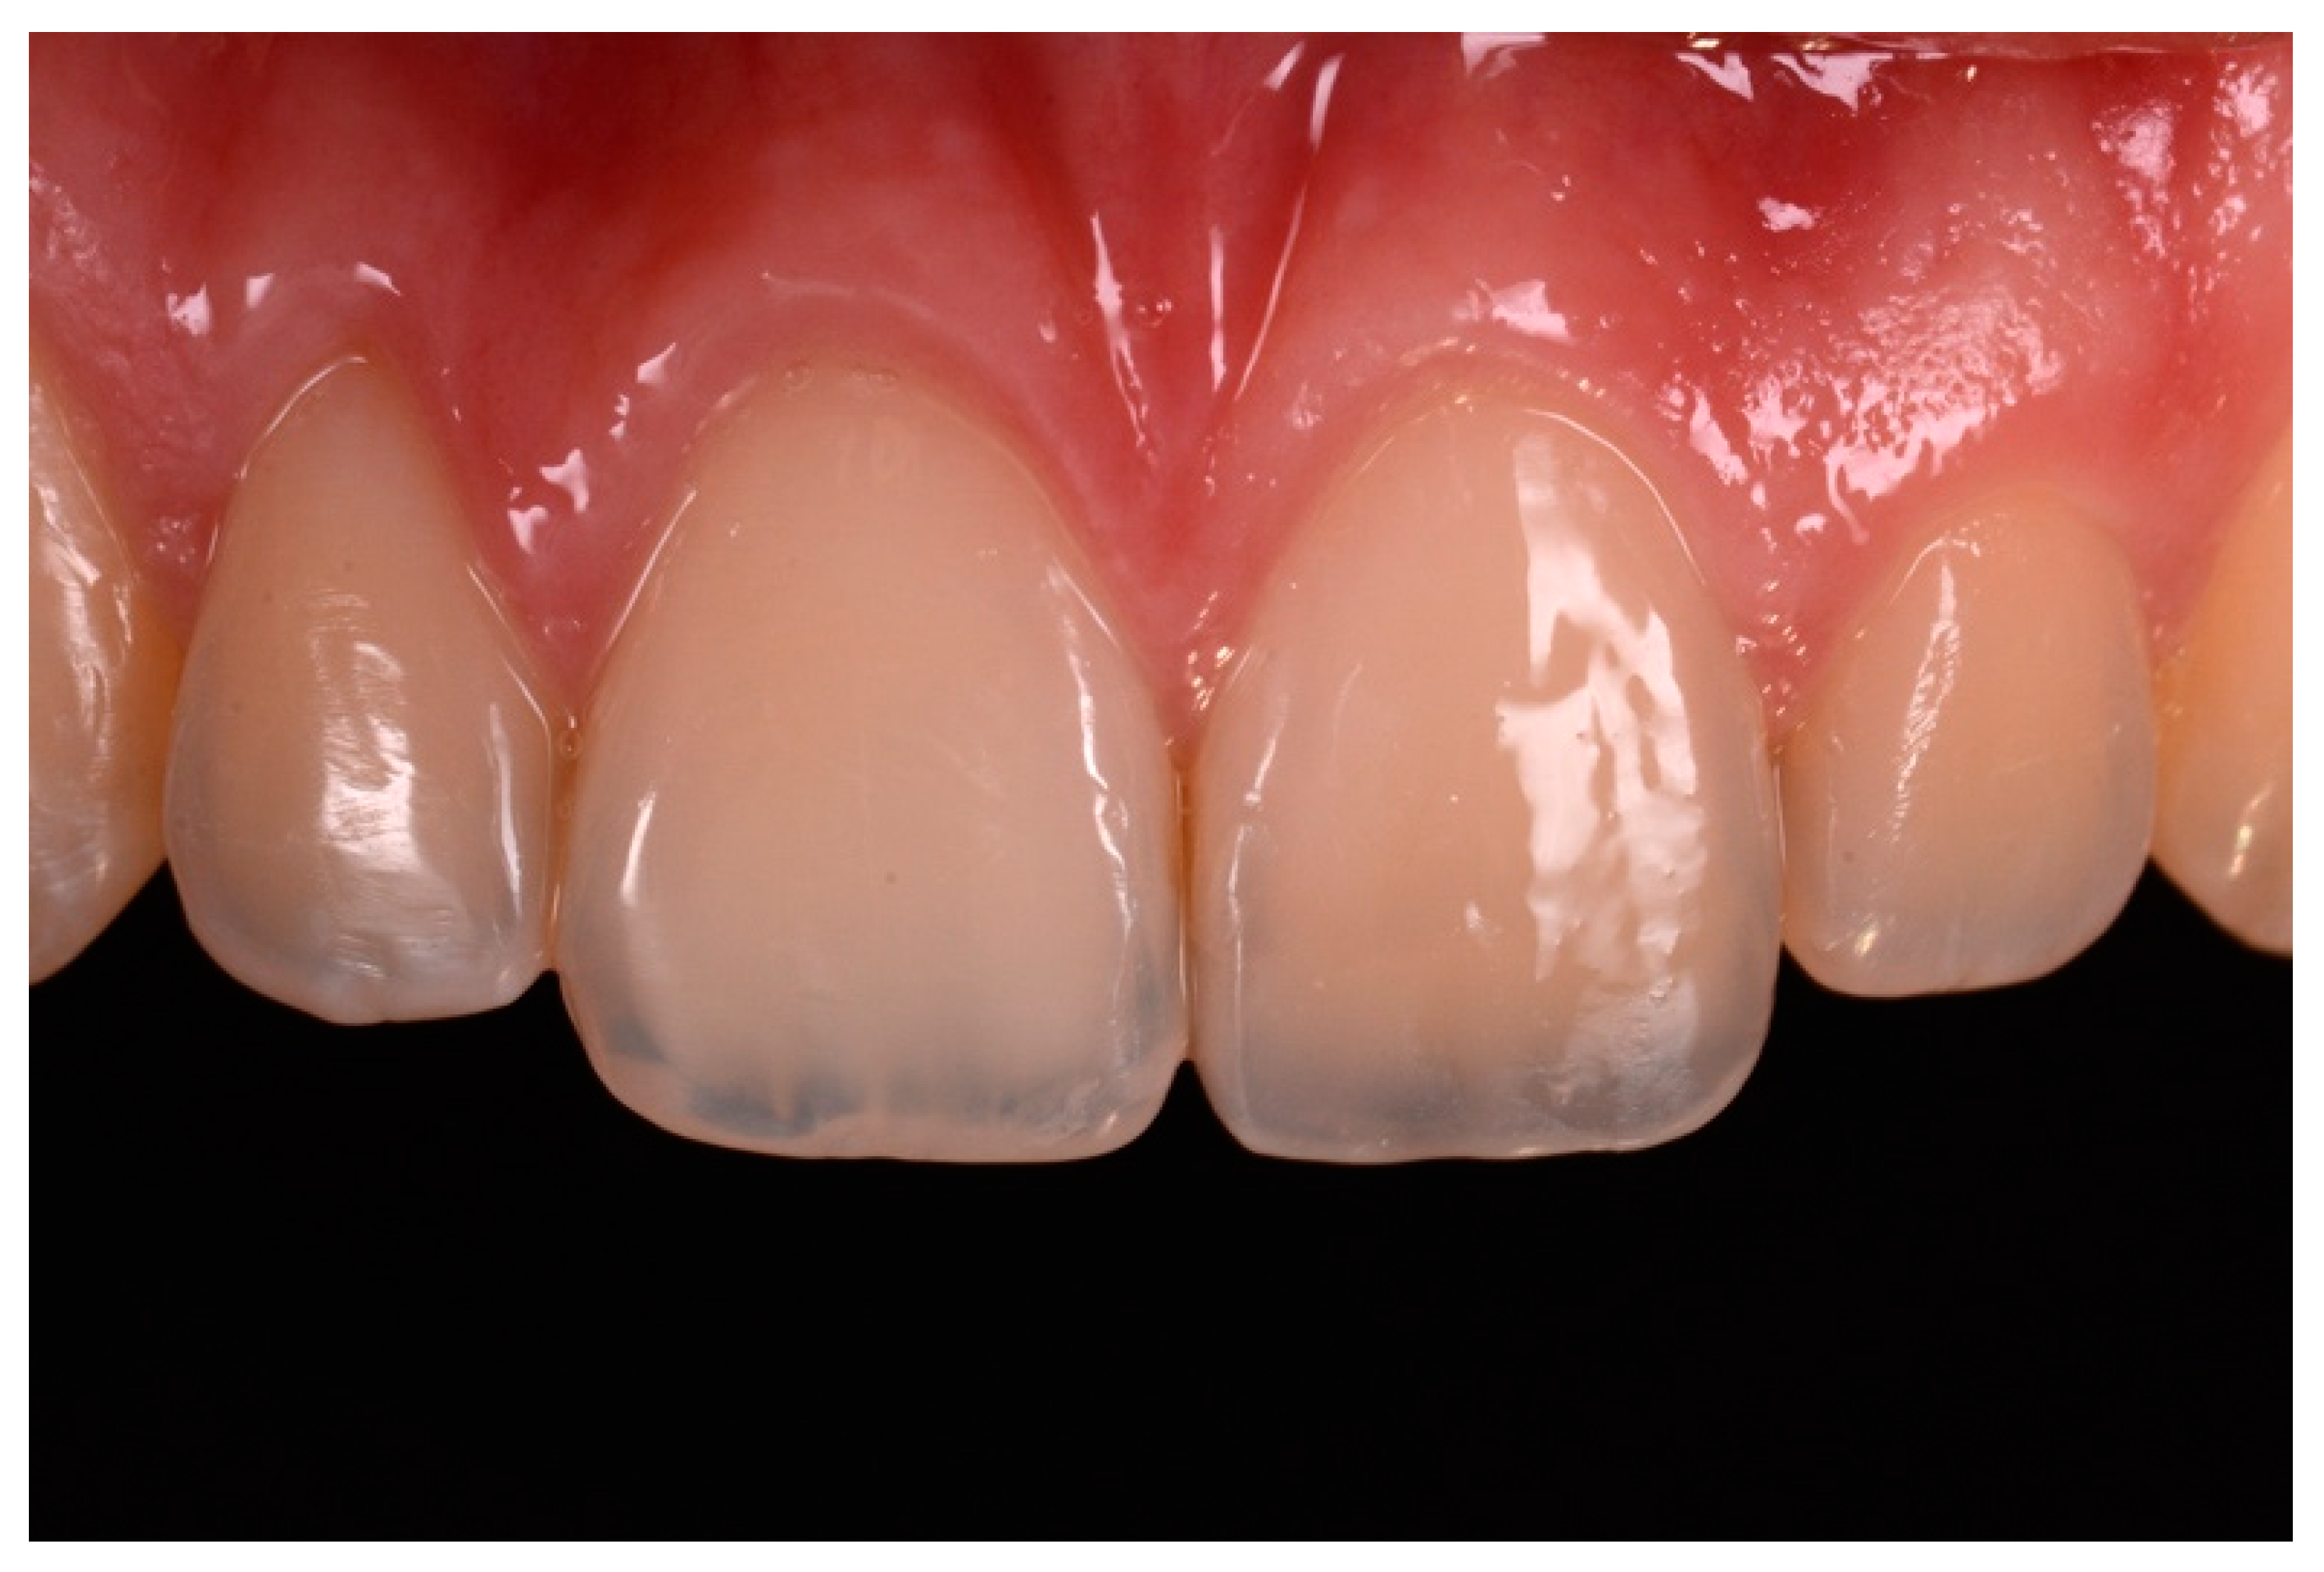

Finishing and polishing procedures were performed with a diamond bur (WL 268 014 Horico, Berlin, Germany), silicone points (Identoflex, Kerr, Bioggio, Switzerland) brushes (Jiffy Goat Air Brushes, Ultradent Products, South Jordan, UT, USA), and diamond pastes (Diamond Polish Mint, Ultradent Products, South Jordan, UT, USA) (Figure 13 and Figure 14). Satisfactory clinical and radiographic outcome was considered satisfactory at 3-months, 1-year, and 5-years post-operative (Figure 15, Figure 16, Figure 17, Figure 18 and Figure 19).

Figure 15.

Three months post-operative. Reprinted from Restauri diretti nei settori anteriori, G. Paolone, S. Scolavino, © 2021, with permission from Quintessence Publishing Italy.

Figure 16.

One year post-operative. Reprinted from Restauri diretti nei settori anteriori, G. Paolone, S. Scolavino, © 2021, with permission from Quintessence Publishing Italy.